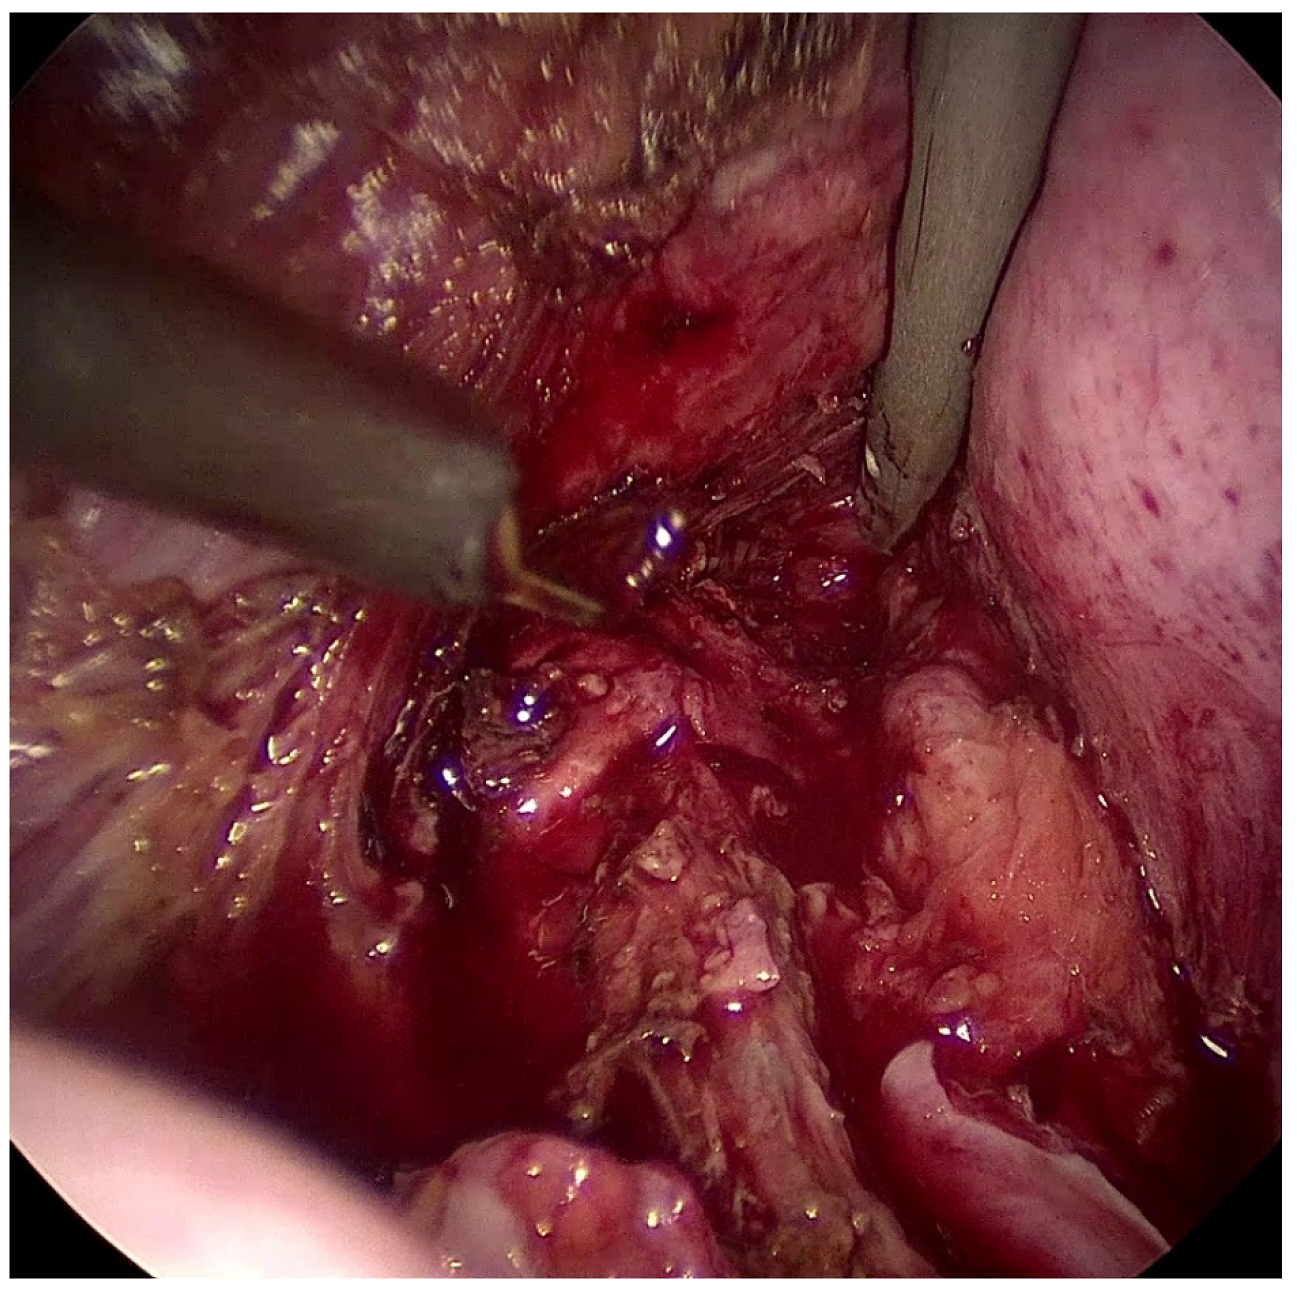

3.1. Case Report